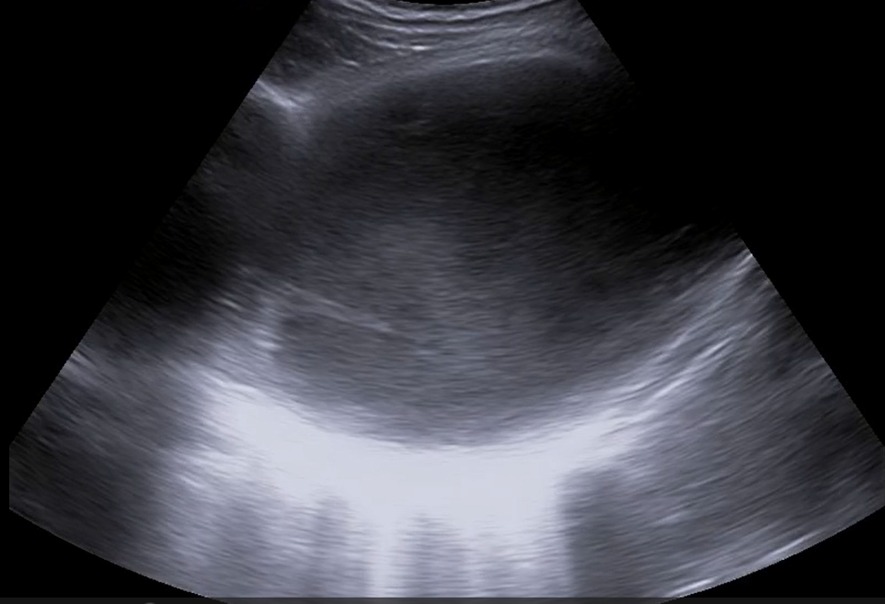

Realizamos ecografía clínica en la consulta objetivando un gran derrame pleural loculado de contenido ecogénico, con finos septos interiores y signo de la espina. Destaca que en el parénquima pulmonar no se observan datos de atelectasia, broncograma aéreo, consolidación ni hepatización, y apenas líneas B.